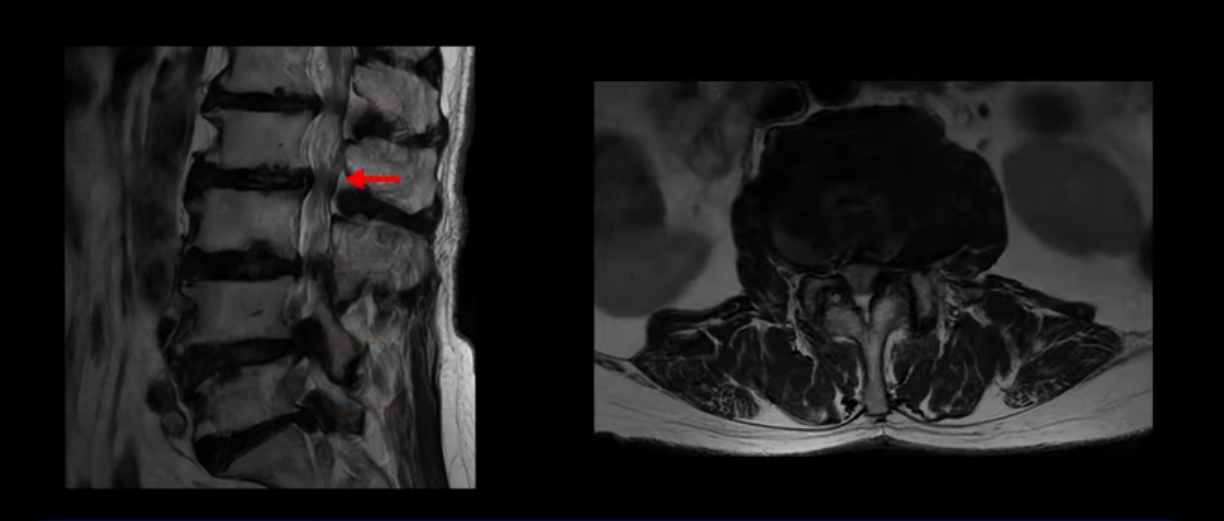

이 환자분은 MRI로 보면 허리 여러 마디가 신경이 매우 심하게 눌려 보이는 분입니다. 이분 MRI를 보면서 간단히 설명해 드린 후 어떻게 이렇게 신경이 심하게 눌린 환자분이 수술 없이 근육신경재활치료로 좋아질 수 있는지, 다리가 아파 걷지 못하는 환자가 어떻게 안 아프고 잘 걸을 수 있게 되는지, 10년 동안 괴로웠던 양 발의 시린 증상은 어떻게 사라질 수 있는지, 치료는 어떻게 하는지 자세히 설명 드리겠습니다.

MRI 보시면 (2-8) 허리의 5마디가 전부 다 심하게 퇴행되어 있습니다.

5마디 전부 다 심한 중심성 협착이 있습니다.

3번 4번,

4번 5번,

이렇게 모두 다 심하게 막히는 경우는 드문데요. 또한 오른쪽, 왼쪽 신경이 빠져나가는 추간공도 다 심하게 막혀있습니다.

오른쪽, 왼쪽 이렇게 신경 구멍들이 다 좁아지고 신경이 눌리니까 양쪽 다리가 발바닥까지 아파서 걷기 어렵고 양쪽 발이 10년 넘게 시린 겁니다. 당연히 수술해서 눌린 신경을 풀어줘야 한다고 들으셨는데요. 이런 환자분을 어떻게 수술 없이 치료할까요? 지금부터 설명해 드립니다.

이분 신경이 눌리는 증상은 오래됐지만, 증상이 아주 심해진 건 올해 들어와서입니다. 그럼, 이분 MRI 영상도 이렇게 심하게 안 좋아진 게 올해 들어와서일까요? 이분의 MRI로 보이는 협착은 아주 오래된 겁니다. 그래서 신경 구멍이 심하게 좁아진 것도 올해가 아니고 오래된 겁니다. 작년, 재작년에 훨씬 덜 아팠을 때 MRI를 찍었어도 신경 구멍 좁은 정도는 별반 차이가 없었을 겁니다.